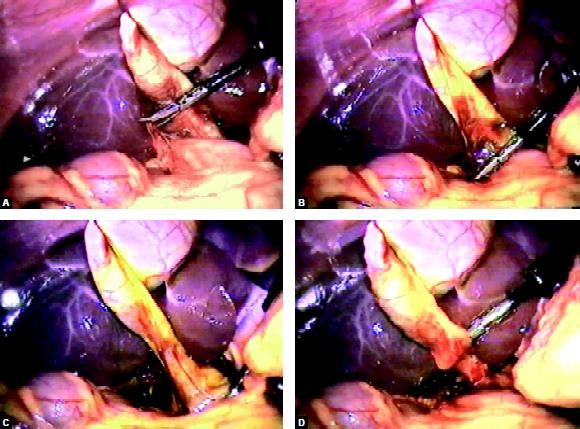

An extracorporeal knot can be applied for a cystic duct without any problem after a nice dissection of the cystic pedicle. The knot which is tied over the cystic pedicle is used to pull the neck of the gallbladder up and with the help of hook GB is separated from the liver. Patients undergoing cholecystectomy by the two-port method had a better resumption of diet and less postoperative pain. Two-port cholecystectomy is technically feasible and may further improve the surgical outcomes in terms of postoperative pain and better cosmetic value. The two-port cholecystectomy should be performed by an experienced laparoscopic surgeon because skilled choreographic hand movement is very important in this surgery. Bimanual skill and correct interpretation of anatomy is a must before proceeding for this technique. We do not recommend two-port cholecystectomy as a routine procedure.

Any leak should be sucked and gallbladder is separated with the help of hook